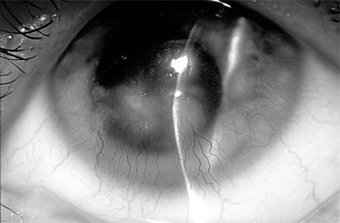

Superior limbic keratoconjunctivitis is usually bilateral and limited to the upper tarsus and upper limbus. The principal complaints are irritation and hyperemia. The signs are papillary hypertrophy of the upper tarsus, redness of the superior bulbar conjunctiva, thickening and keratinization of the superior limbus, epithelial keratitis, recurrent superior filaments, and superior micropannus (Figure 5-19). Rose bengal staining is a helpful diagnostic test. The keratinized epithelial cells and mucous debris pick up the stain. Scrapings from the upper limbus show keratinizing epithelial cells.

Figure 5-19

Figure 5-19: Superior limbic keratoconjunctivitis. Note the "corridor" on the bulbar surface.